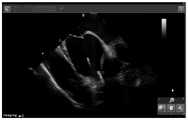

图5是示例房间隔穿刺鞘组合沿导丝上行过程中淹没部分导丝;Figure 5 is an example of submerged part of the guide wire during the ascent of the transseptal sheath combination along the guide wire;

②沿导丝将房间隔穿刺鞘组合送入上腔静脉,并逐渐淹没高亮度的导丝影。(见图5)②The interatrial puncture sheath was combined into the superior vena cava along the guide wire, and the high-brightness guide wire shadow was gradually submerged. (see Figure 5)